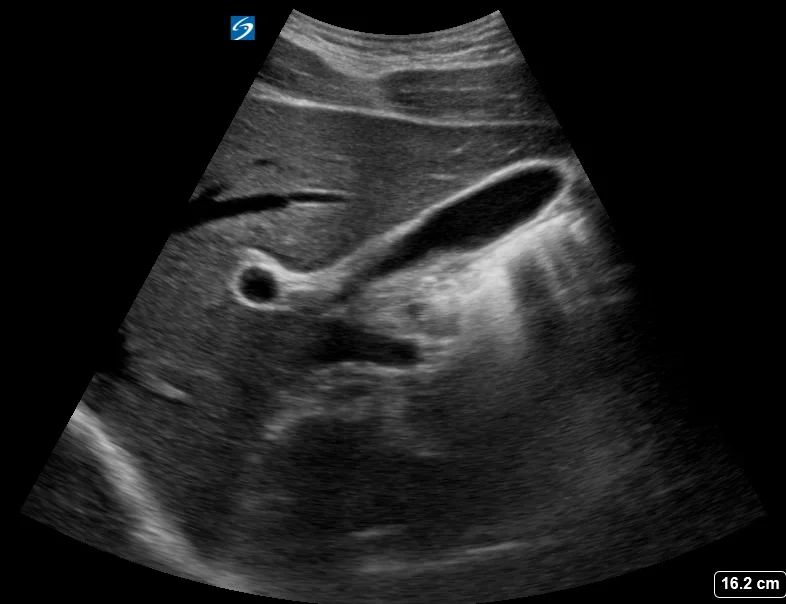

What is this sign? What vessels are involved?

Seagull sign.

Celiac artery, splenic artery, hepatic artery.